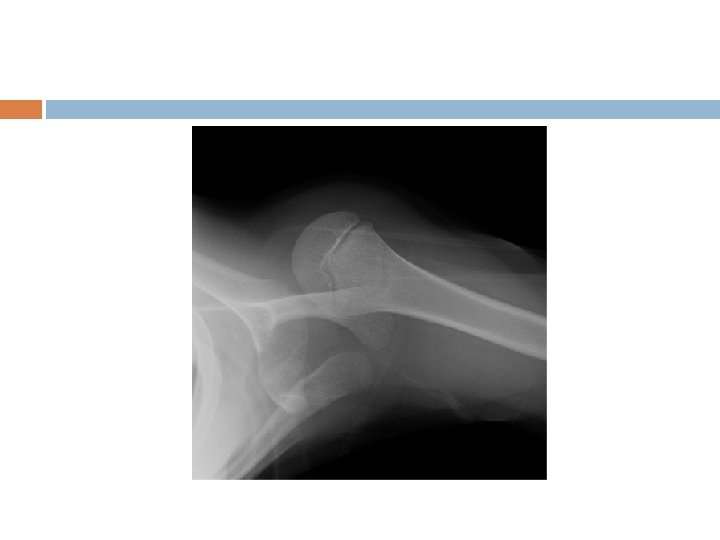

Scapular-Y

Anterior Instability Exams-Apprehension -Relocation -Load and Shift Diagnostics-X-ray Views: AP, axillary and scapular-Y -can be performed before for diagnosis or after reduction for confirmation of relocation depending on clinical setting